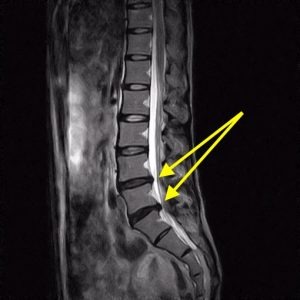

ヘルニアの画像診断

腰椎椎間板ヘルニアは下記の画像の矢印部分のような軟骨の飛び出しが見られます。